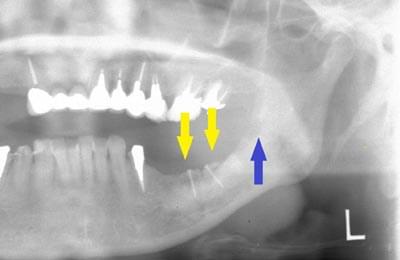

患者様の治療前のレントゲン写真です。写真の黄色矢印部の歯の周囲は、重度の歯周病で大きく歯槽骨が吸収されてしまっていました。そのため、写真の、赤色矢印で示す、下顎骨の中を通る神経までの距離がなく、インプラント埋入には、骨の高さが不足していました。

インプラントを埋入するためには、骨を増やさなければならず、患者様ご自身の骨を移植する、自家骨移植術を行なうこととしました。写真、青色の矢印で示す、智歯周辺の骨を採取し、黄色の矢印の部位に骨片を移植、チタン製の小さなスクリューで骨片を固定するという手術を行いました。細く、白く映っているのが骨を固定したミニスクリューです。